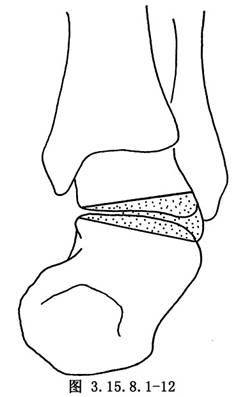

6.5.3 3.截骨矫形

先用骨刀截除跟骰关节和距舟关节,楔形截骨基底在背外侧纠正内翻畸形(图3.15.8.1-8),切除角度等于X线片第2趾和足中线形成的角度(图3.15.8.1-9)。若纠正足外翻畸形,楔形截骨基底可设计在内侧(图3.15.8.1-10),由于距舟关节和跟骰关节在一个平面上,切除角度是一致的(图3.15.8.1-11)。最后切除距下关节,纠正跟骨内收(图3.15.8.1-12),根据X线片胫骨中线和跟骨中线形成的角度,做外侧楔形切除(图3.15.8.1-13)。当骨刀切到对侧时,注意轻缓,尤其纠正外翻时,更要注意防止误伤胫后的血管及神经(图3.15.8.1-14)。将已切除的骨面合拢,如畸形纠正,骨面能紧密对合(图3.15.8.1-15),周围空隙植入切除多余的松质骨。